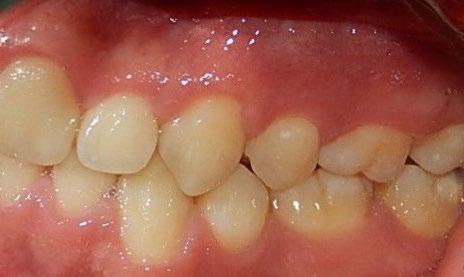

Se presenta un paciente de 18 años de edad que refiere tener hemofilia tipo A, moderado grado V. En los estudios de inicio extraorales, se observa en la Figura 1 el frente, sonrisa y perfil. En la radiografía lateral de inicio (Figura 2) se evidencian el overjet y overbite reducidos, clase I esquelética, hiperdivergencia y biprotrusión dentoalveolar.

En los estudios intraorales, las fotografías iniciales muestran clase I canina y molar bilateral, mordida anterior abierta, apiñamiento leve superior e inferior, y líneas medias dentales

desviadas. En las Figuras 4, 5 y 6 se observa la forma de las arcadas superior e inferior.

Figura 4. Lateral derecha.

Figura 5. Intraoral de frente e izquierda.

Figura 6. Oclusal superior e inferior de inicio.